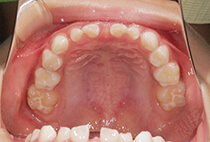

20代女性の患者さま。

八重歯の見た目が気になってご来院されましたが、実は顎の痛みや開口障害など、顎関節症の症状もありました。

そのため、かみ合わせと顎関節症の治療を同時に行ったにもかかわらず、2年間で治療が終了。

かみ合わせが整い咬筋の過緊張も改善しました。咬筋の肥大も治ってフェイスラインがすっきりしました。

最終的には美しい歯並びと、安定した痛みのないかみ合わせが実現しました。

八重歯が気になる

叢生、顎関節症、開口障害

20代女性

矯正治療2年

唇側矯正

矯正:1,161,600円+毎月調整量:6,050円

しっかり前歯を下げるために、インプラントアンカーを使用してコントロールしました。

かみ合わせが整うと咬筋の過緊張が改善。

過緊張による筋肉肥大も改善しフェイスラインもすっきりしました。